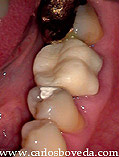

5 años más tarde la paciente nos es referida nuevamente para evaluar la condición presente y dar nuestra opinión endodóntica, pues se da el caso que ha perdido completamente la porción coronal de su diente y su Odontólogo requiere en principio de espacios en los conductos para alojar pernos que puedan dar retención a una nueva reconstrucción. Observense las imágenes clínicas y radiográficas siguientes que ilustran la nueva condición del diente:

Estamos completamente de acuerdo con la perspectiva de indicar una repetición del tratamiento endodóntico si por alguna razón ha estado expuesto al medio bucal. Sin embrago, si se detallan las imágenes clínicas y particularmente las radiográficas (donde se evidencia la diferente radiopacidad en la porción coronal de los conductos), se apreciará que se mantuvo el sellado con vidrio ionomérico aún cuando se perdió la corona clínica del diente.

La problemática pasa a ser entonces de carácter restaurador, dado lo estrecho, pequeño y curvo de los conductos presentes, donde una retención tradicional con pernos en el interior de los conductos, puede llevarnos no solo a debilitar innecesariamente la estructura dentaria, si no además se presta a un accidente (por ejemplo perforación, fractura radicular posterior, etc...).

Por otra parte, dadas las virtudes de los sistemas adhesivos actuales, podemos pensar en una reconstrucción coronal completamente adhesiva y retenida además en una pequeña porción de los conductos.

Una vez aislado el caso y confirmada la ausencia de filtración coronal en los conductos, así como las adecuadas condiciones periodontales, se elimina el bloqueo de vidrio ionomérico y se descubren los conductos.